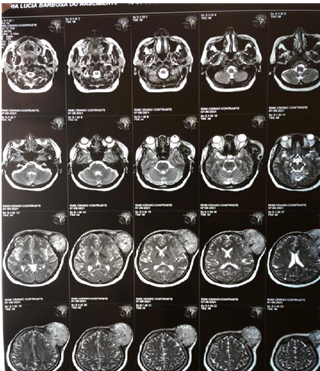

Figure 5A Contrast-enhanced magnetic resonance image showing a tumor in the extraaxial region of left frontal involvement with axial section.

Figure 5B Contrast-enhanced magnetic resonance imaging showing a tumor in the extraaxial region of left frontal involvement.

Figure 6A Contrast-enhanced magnetic resonance imaging showing a tumor in the extraaxial region of left frontal involvement.

Figure 6B Contrast-enhanced magnetic resonance imaging showing a tumor in the extraaxial region of left frontal involvement.